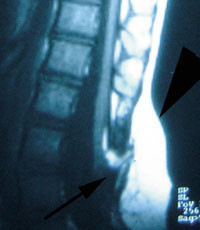

Spinale lipomer

Spinale lipomer er svulster av fett- og bindevev med forbindelse til ryggmargen. De kan være komplett intradurale, men hyppigst finner man et subkutant lipom i kontakt med ryggmargen via defekter i lumbosakralfascien og bakre bue av ryggvirvelen (fig 3) (3).

Lipomets tilheftingspunkt varierer og kan finnes i lumbosakralmedulla, conus medullaris eller filum terminale (1, 3). På grunn av tilheftingen medfører et spinalt lipom risiko for ryggmargstjoring (tethered cord).